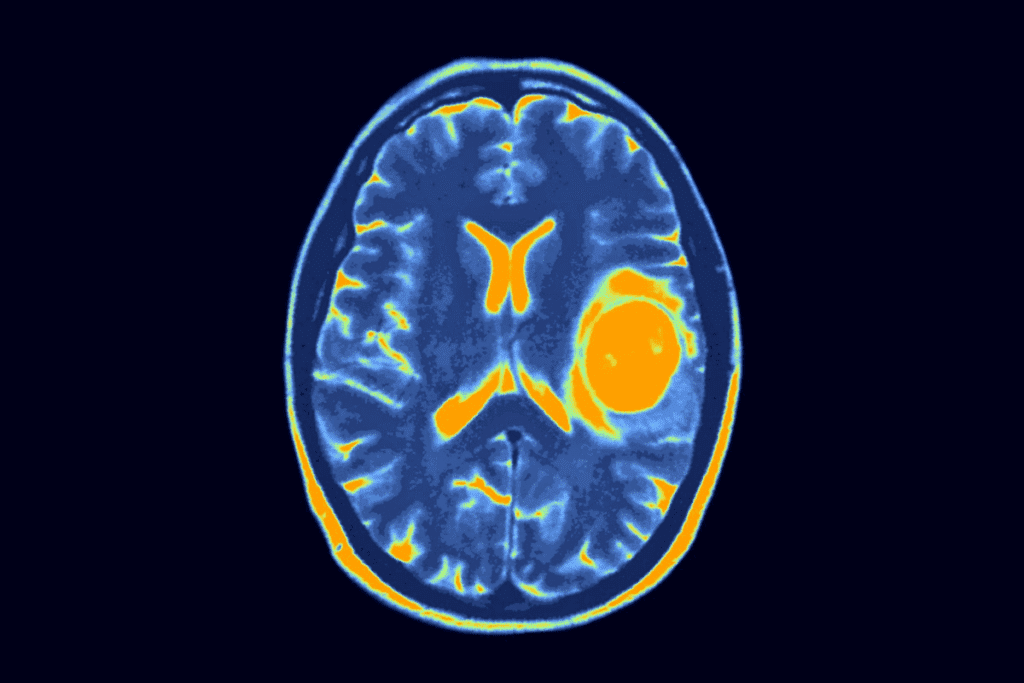

What MRI Can Reveal About Brain Tumors

MRI gives a lot of info about brain tumors. It shows where they are, how big they are, and what they’re like. Advanced MRI can also look at how tumors work and their blood supply, helping doctors plan treatment.

MRI can tell if a tumor is harmless or cancerous by looking at its edges and how it affects the brain. This info is vital for doctors to decide the best treatment.

Interpreting MRI Brain Tumor Results

Reading MRI results for brain tumors is a detailed job for skilled radiologists. They carefully look at the MRI images for any signs of tumors. This helps them understand what the images show.

How Radiologists Analyze Brain MRI Images

Radiologists follow a specific method to study brain MRI images. They check the size, shape, and where the abnormalities are. They also look at how these appear on different MRI sequences. This helps them figure out if the abnormalities are likely tumors.

They examine several things, including:

- Size and Location: Larger tumors or those in key areas are more concerning.

- Signal Intensity: Tumors can look different on MRI images based on their tissue.

- Contrast Enhancement: Contrast agents can make tumors more visible.

- Margins and Edema: The edges of a tumor and swelling around it give clues.

Common Findings That Indicate Tumors

Some patterns and features on MRI images suggest brain tumors. These include:

- Mass Effect: Tumors can push or distort normal brain structures.

- Heterogeneous Enhancement: Tumors may show different enhancement patterns after contrast.

- Necrosis: Necrotic areas in a tumor can indicate aggressive growth.

By studying these signs, radiologists can give important information. This helps in diagnosing and managing brain tumors.